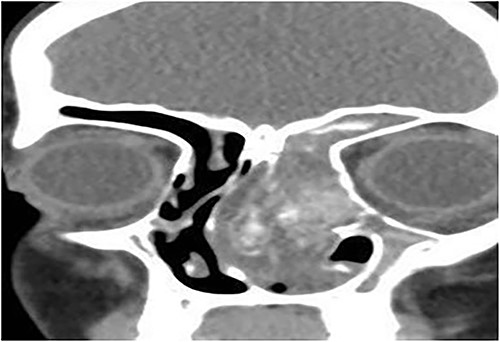

A 13-year-old male presented with progressive right-sided nasal obstruction followed by slowly progressive right eye proptosis noticed by parents for 1 year duration. CT scan of the paranasal sinuses (Fig. 2) confirmed the diagnosis of AFS. The child underwent FESS and received medical treatments post-operatively. The patient remained symptom-free for 4 years follow-up.

Axial CT paranasal sinuses shows the right ethmoid and sphenoid sinuses with complete obliteration and hyperdense (metallic) contents. It is associated with expansion of the ethmoid sinuses and lateral displacement of the right lamina papyracea causing right eye proptosis.